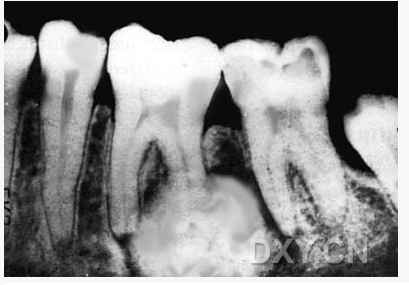

骨髓炎

含牙囊腫